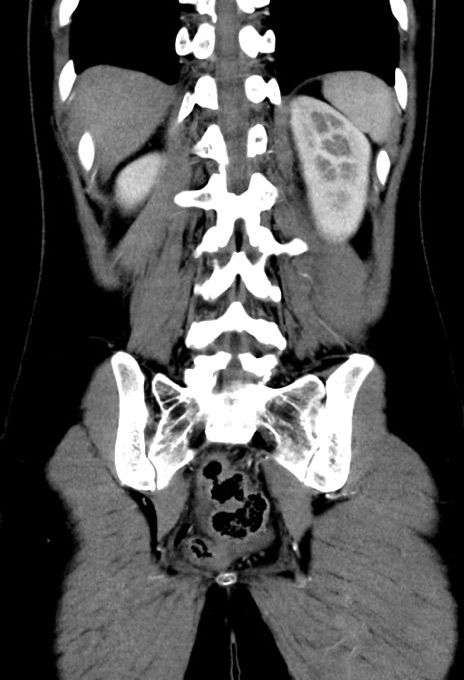

症例17(冠状断像)

【症例】20歳代女性

【主訴】嘔吐、下腹部痛

【現病歴】昨日夕食後に嘔吐し下腹部痛が出現。本日になっても嘔吐持続し改善しないため来院。

【身体所見】意識清明、BT 37.2℃、BP 108/67mmHg、腹部:平坦、やや硬、下腹部正中から右にかけて圧痛あり、反跳痛軽度あり、tapping pain(+)。

【データ】WBC 13600、CRP 14.94